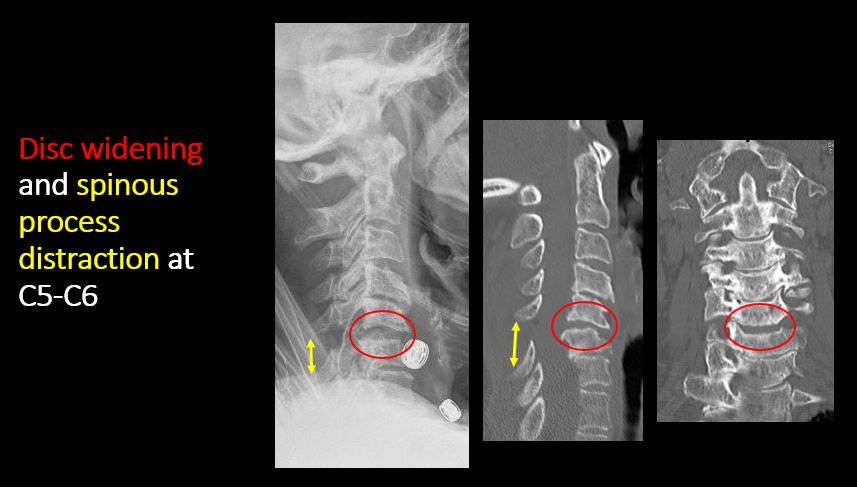

There is distraction or focal widening of a disc space. |

Yes | NA |

Limited flexion and extension views show evidence of ligamentous injury at C5-C6 with kyphotic deformity, bilateral perched facets, and rotational deformity. Mild anterior wedging of C5 is likely chronic.

Direct communication with the clinical team at the time of dictation regarding ligamentous injury and perched facets at C5-C6.